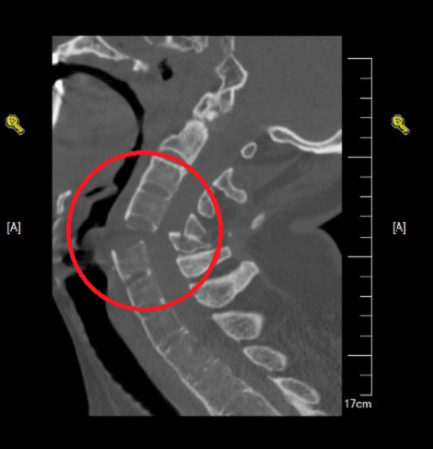

颈椎是我们人体脊柱的一部分,上承头颅,下接胸椎,脊椎神经都从这里经过,它的损伤将直接危及生命。去年7月1日,患者李某因为外伤导致四肢瘫痪,被救护车送到曙光医院,急诊CT检查发现,颈椎5-6脱位,情况危急。

▲颈椎严重骨折